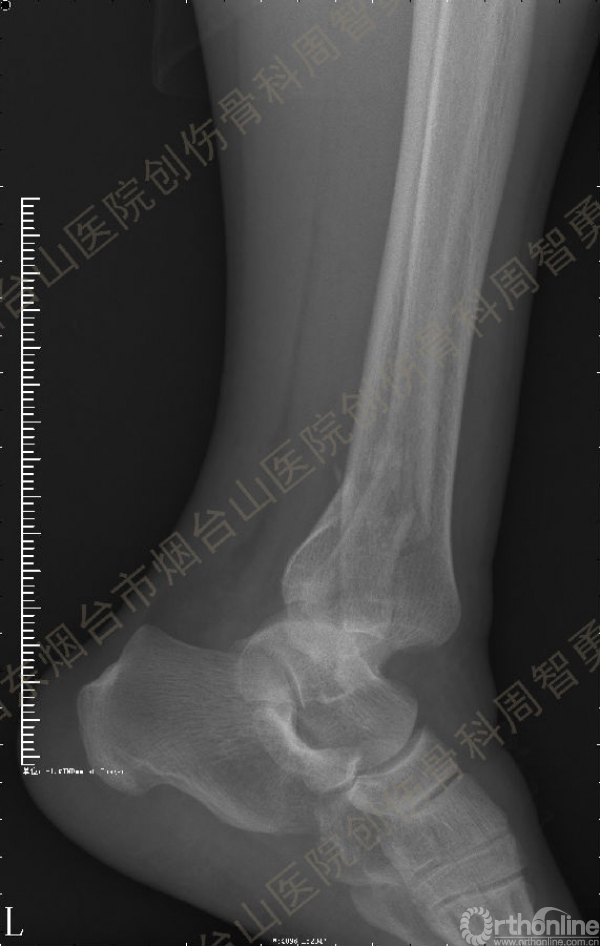

患者一般情况可,左踝关节肿胀,见皮下瘀斑,内、外、后侧有压痛,左踝关节主动运动受限,左足皮肤感觉、血供未见明显异常,左足趾各关节可主动运动。左踝关节正位X线片和CT重建示内踝内上方双层骨皮质影(图1a,c),CT示后侧骨折块分为后内侧骨折块和后外侧骨折块(图2a,b),后内侧骨折块累及内踝后丘,后丘骨折线呈冠状位(图2c),后内侧骨折块腹侧有向近端塌陷的小块骨软骨骨折块(图2d),CT也显示Chaput骨折块(图1c,2e)。

经典的后踝骨折发生于低能量旋转外力所致的踝关节骨折;标准pilon骨折见于高能量轴向暴力;而后侧pilon骨折是旋转外力和轴向暴力共同作用的结果,属于中等能量的损伤。踝关节骨折中的后踝骨折源自下胫腓后韧带的牵拉,骨折块位于后外侧,常为单一的三角形骨折块,大小从关节外片状骨折到累及胫骨远端关节面矢状径的40%(图4a)。后侧pilon骨折中的后侧骨折块较大,累及内踝后丘(三角韧带深层起点)在内的整个胫骨远端后侧,分为后内侧骨折块和后外侧骨折块,后内侧骨折块腹侧有向近端塌陷的骨软骨骨折块(图4b)。后侧pilon骨折中的内踝骨折线并不是水平位而是冠状位,可合并内踝前丘骨折。后侧pilon骨折踝关节正位X线片示特异性的内踝内上方双层骨皮质影(图1a,c)。这是由于后内侧骨折块的骨折线延伸到胫骨远端骨骺和干骺端的内侧骨皮质,其移位后的边缘成像所致。水平位CT显示后侧骨折块分为后内侧骨折块和后外侧骨折块,矢状位CT示后内侧骨折块腹侧有向近端塌陷的骨软骨骨折块。

↑图 1c

图 1 术前左踝关节正侧位X线片和CT重建,箭头所示内踝内上方双层骨皮质影(a,c)

图 2 术前CT,显示后侧骨折块分为后内侧骨折块和后外侧骨折块(a,b),后内侧骨折块累及内踝后丘,后丘骨折线呈冠状位(c),箭头所示后内侧骨折块腹侧有向近端塌陷的小块骨软骨骨折块(d),Chaput骨折块(e)